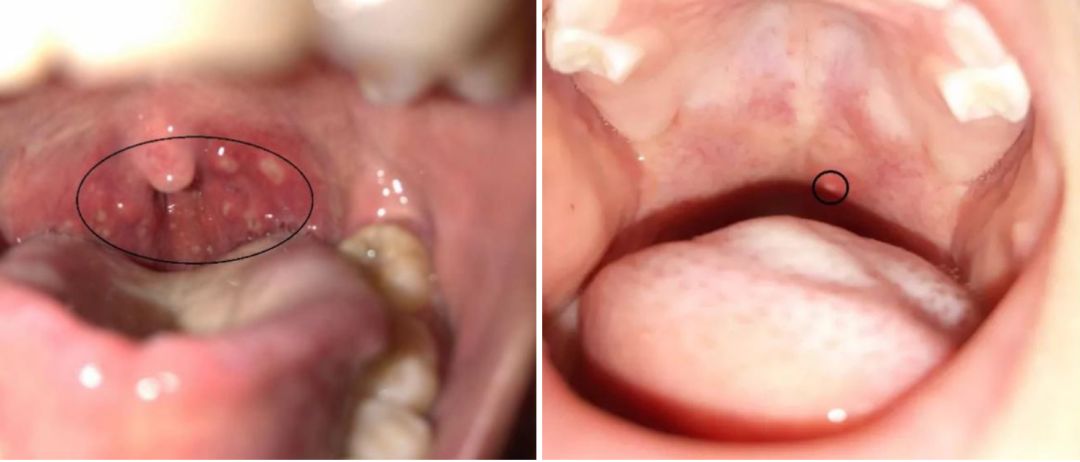

疱疹性咽峡炎/图源怡禾健康

口腔皮疹主要集中在靠前的位置,舌头、颊黏膜较多,同时手足或者臀部可以看到皮疹。

疱疹性咽峡炎:

口腔皮疹以喉咙部位多见,位置相对靠后,不伴有四肢臀部等部位的皮疹。